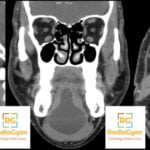

Radiology Volume Calculator Ovary Prostate Bladder Spleen Kidneys Etc Radiogyan